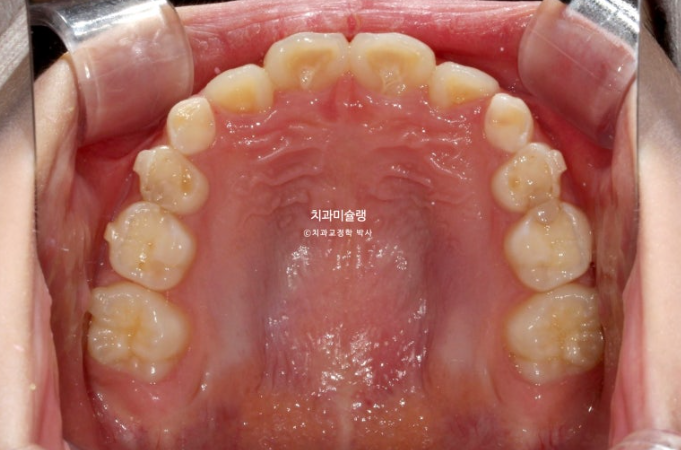

23년 10월, 교정치료를 위해 온 어린이 입니다.

앞니 두 개 높낮이 차이, 앞니가 깊게 물리는 과개교합이 보입니다.

앞니 네개 중 옆 앞니 즉 측절치가 나올 공간이 좁습니다.

어린이 교정은 악궁확장을 통해 이가 날 공간을 넓히는 과정이 동반이됩니다.

인비절라인 퍼스트 치료에 들어갔습니다.